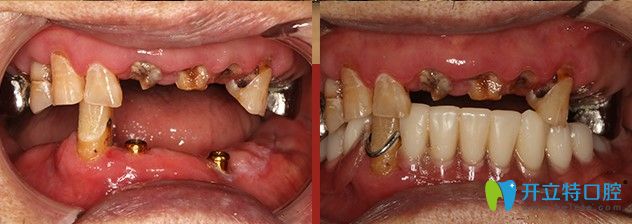

廣大口腔給韓重聲老人做種植牙的前后對比圖

顧客姓名:韓重聲/100歲

顧客身份:“解放戰(zhàn)爭、抗美援朝戰(zhàn)爭”功勛老軍人

顧客癥狀:上頜存牙較多,下頜僅剩五顆牙齒,四顆均有炎癥

治療方案:“高齡精準(zhǔn)種”,即刻負(fù)重

主治醫(yī)生:侯國鎮(zhèn)主任

一生辛勞,誰都想安享晚年,老有口福。為種一口好牙,韓重聲老人早早來到了“高齡精準(zhǔn)種”發(fā)布會現(xiàn)場。發(fā)布會結(jié)束后,老人來到了精準(zhǔn)種植中心,韓老剛來到廣大口腔想要做種植的時候,口腔狀況并不樂觀。